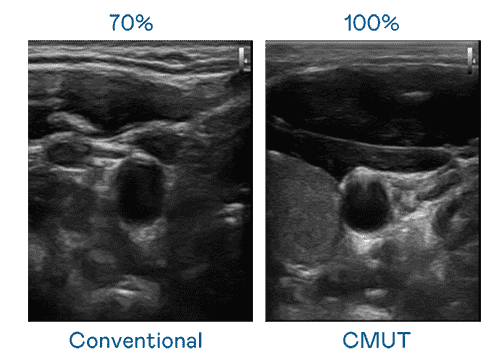

CMUT 技术是一种用电容式微机电元件来产生超音波讯号的技术。。。与传统 PZT 压电式技术相比,,,CMUT 频宽增加 30%,,,,更宽频的超音波讯号让影像解析度大幅提升,,,,是实现高影像品质医疗超音波扫描、、、、促进精准医疗发展的关键技术。。

大频宽带来超清晰影像

超音波影像的解析度高低,,,首先取决于探头能发出的讯号频宽。。。CG电子 CMUT 可提供高清晰的超音波讯号,,,提供高频宽、、、高灵敏度、、、影像纹理细节更高的超音波影像,,,协助医护人员缩短影像判读时间及利用精准的医疗影像进行诊断。。。